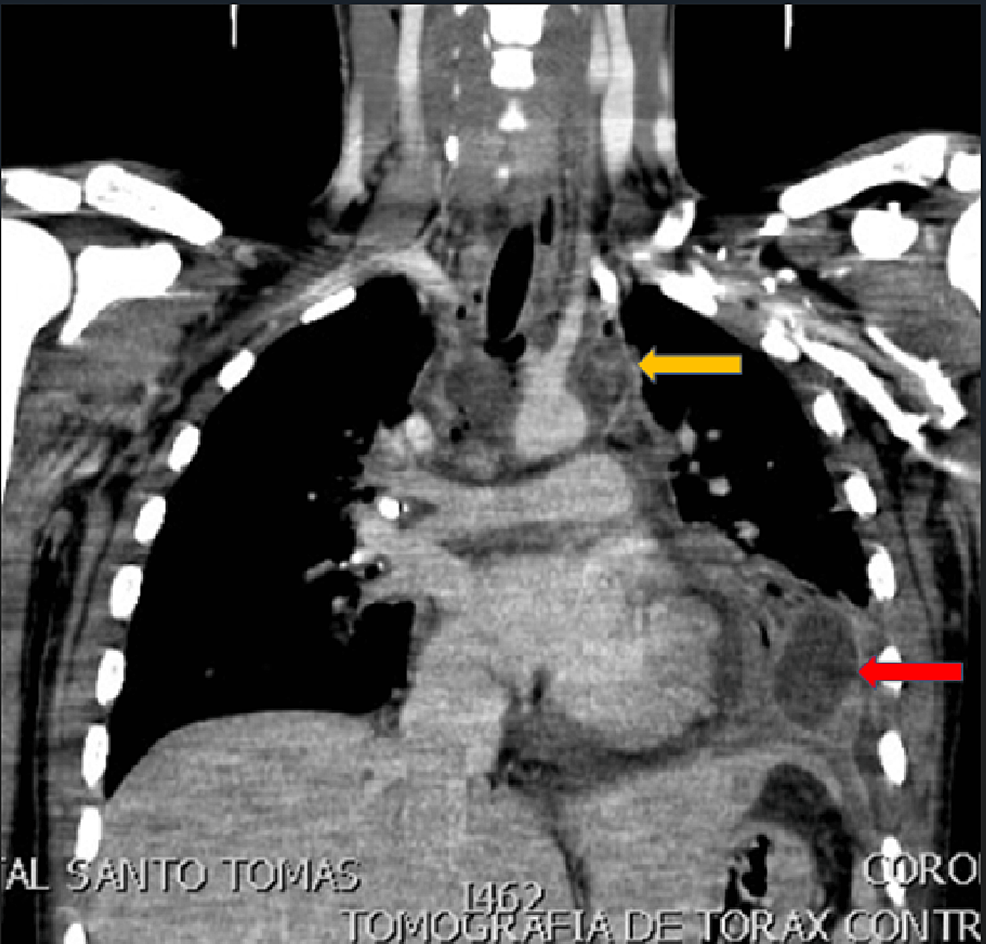

Descending Necrotizing Mediastinitis by Streptococcus anginosus and Prevotella buccae in an Intensive Care Unit Patient: A Case Report

Necrotizing infections of deep neck spaces are a group of life-threatening infectious diseases acquired through trauma or as a descending infection from an odontogenic source. The isolation of pathogens is...

We present a case of a patient without risk factors for descending necrotizing mediastinitis with isolation of Streptococcus anginosus and Prevotella buccae managed at the intensive care unit with a multidisciplinary team. We present our approach and how we successfully treat this complicated infection.